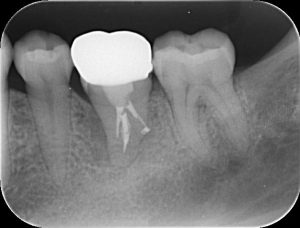

下の写真は、内部でむし歯が進行し、クラウン(被せ物)が脱離している状態です。

すべてのむし歯を除去すると、残存する歯質が薄くなり、その後の破折リスクが高いと判断し、抜歯をすることになりました。

抜歯後の治療方法に関しては、最後方に親知らずが存在しており、噛んでいる歯もありませんでしたので、いくつかの検査を経て、歯の移植が可能と判断し、治療を進めることになりました。

移植後1ヵ月程で根管治療を開始し、数ヵ月間経過観察を行い、ジルコニアクラウンを装着しました。(写真は、仮着中の時のものなので、内側に撤去用の突起がついています。)